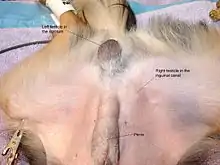

In the minority of cases with bilaterally nonpalpable testes, further testing to locate the testes, assess their function, and exclude additional problems is often useful. Scrotal ultrasound or magnetic resonance imaging performed and interpreted by a radiologist can often locate the testes while confirming absence of a uterus. At ultrasound, the undescended testis usually appears small, less echogenic than the contralateral normal testis and usually located in the inguinal region. With color Doppler ultrasonography, the vascularity of the undescended testis is poor.

In cases where the testes are identified preoperatively in the inguinal canal, orchiopexy is often performed as an outpatient and has a very low complication rate. An incision is made over the inguinal canal. The testis with accompanying cord structure and blood supply is exposed, partially separated from the surrounding tissues ("mobilized"), and brought into the scrotum. It is sutured to the scrotal tissue or enclosed in a "subdartos pouch". The associated passage back into the inguinal canal, an inguinal hernia, is closed to prevent reascent. In patients with intra-abdominal maldescended testis, laparoscopy is useful to see for oneself the pelvic structures, position of the testis and decide upon surgery (single or staged procedure ).